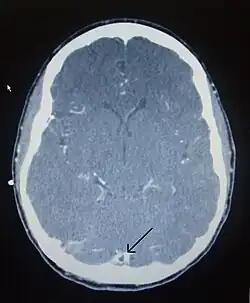

Computed tomography, with radiocontrast in the venous phase (CT venography or CTV), has a detection rate that in some regards exceeds that of MRI. The test involves injection into a vein (usually in the arm) of a radioopaque substance, and time is allowed for the bloodstream to carry it to the cerebral veins – at which point the scan is performed. It has a sensitivity of 75–100% (it detects 75–100% of all clots present), and a specificity of 81–100% (it would be incorrectly positive in 0–19%). In the first two weeks, the "empty delta sign" may be observed (in later stages, this sign may disappear).[11] The empty delta sign is characterized by enhancement of the dural wall without intra-sinus enhancement.[6]

Magnetic resonance venography employs the same principles, but uses MRI as a scanning modality. MRI has the advantage of being better at detecting damage to the brain itself as a result of the increased pressure on the obstructed veins, but it is not readily available in many hospitals and the interpretation may be difficult.[11]